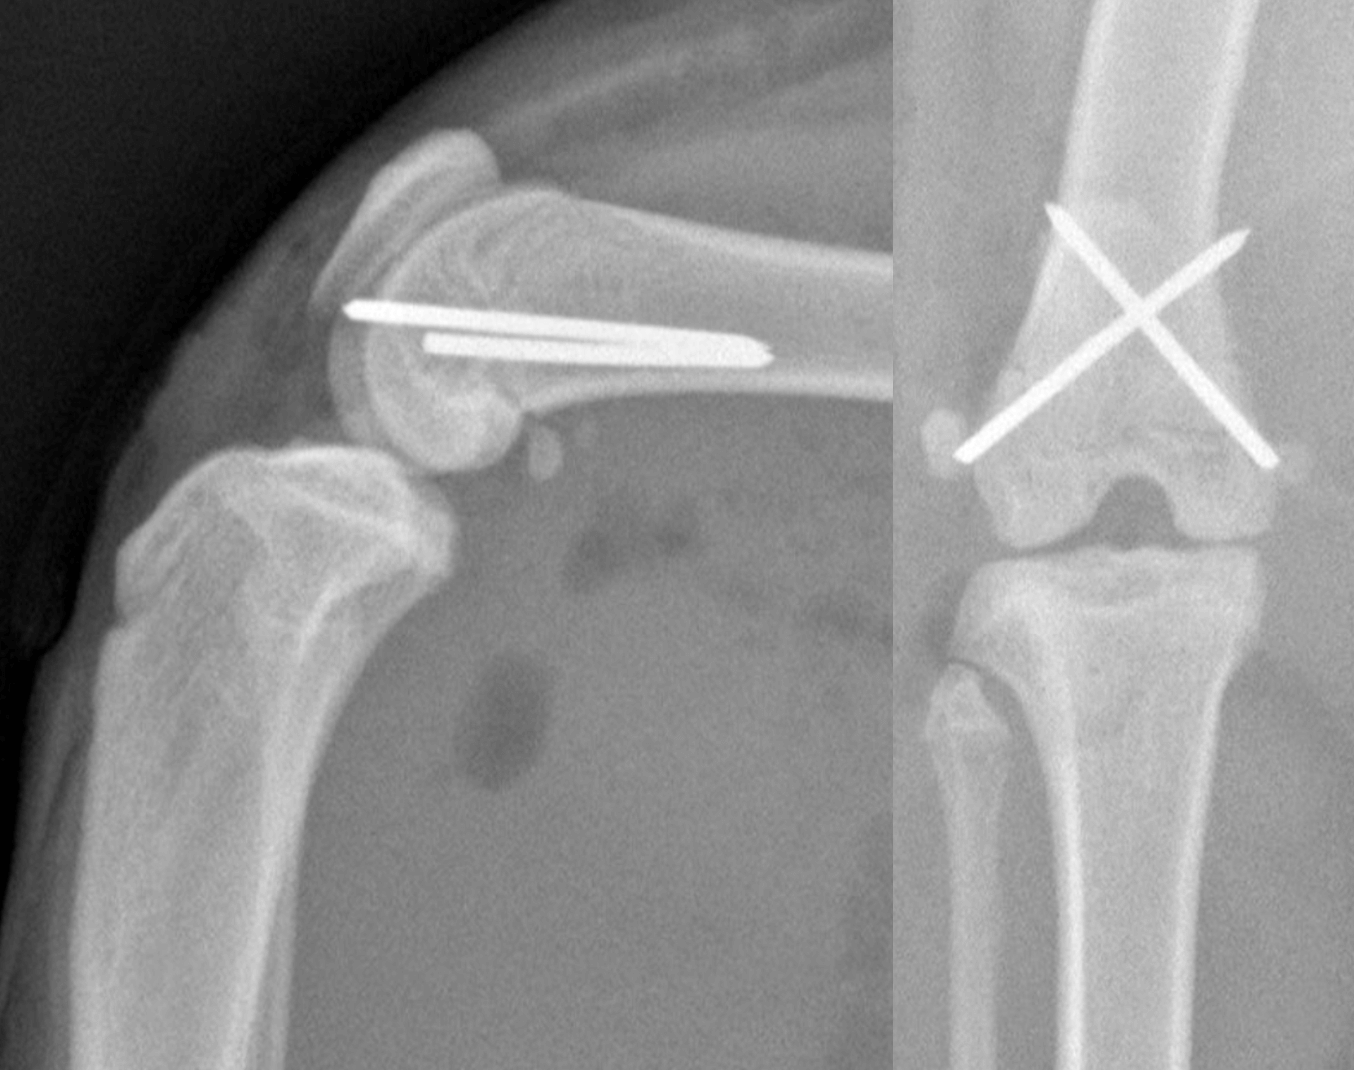

Fracture Salter Harris Type I du femur distal chez Olaf traitée par un brochage en croix (profil et face)

Fracture Salter Harris type IV de l’humerus distal sur Yuki traité par vis intercondylienne et une plaque LCP latérale. (face et profil )